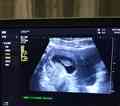

试管婴儿取卵过程会经历促排卵和卵泡监测两个环节,等到女性卵泡成熟后再进行取卵。取卵的主要方法是,在进行局部麻痹后,使用取卵针经阴道B超引导,穿过阴道穹窿,直达卵巢吸取卵子,然后将取出的卵子移到含胚胎培养液的培养皿中,置37°C的培养箱中培养。